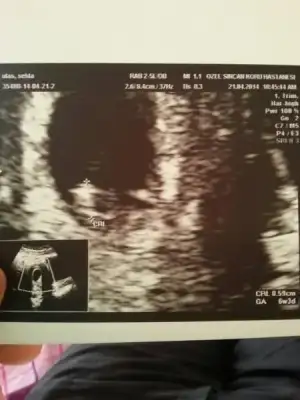

Facebook grubumuza koymustum burayada koymak iatedim evet bebisim 6+1

Eklentiler

• $1398100145128.webp

$1398100145128.webp

15,6 KB · Görüntüleme: 39